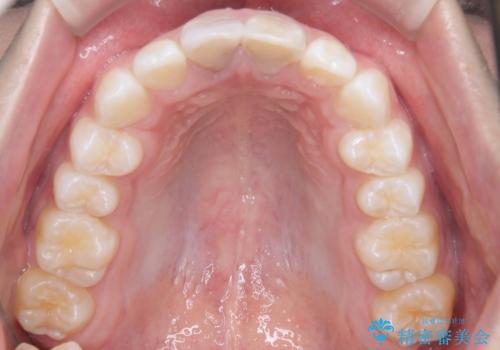

【ワイヤー矯正 11ヵ月で矯正終了!】歯のでこぼこを治したい!

- 「歯のでこぼこを治したい 1年くらいで矯正を終わらせたい」を主訴に来院された患者様です。

叢生量は多く無く歯の傾斜も標準傾斜だったので歯は抜かずにワイヤー矯正で治療を行いました。

左側は2級傾向が強く臼歯の遠心移動をご提案しましたが、1年以内に矯正を終わらせたいという患者様のご意向で希望されず叢生を改善する矯正となりました。